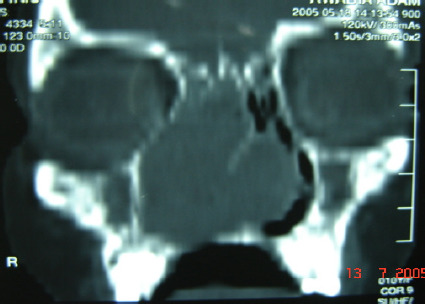

Background: Cellular schwannoma is a benign variant of classic schwannomas. It is an extremely rare condition to be derived from nasal septum.

Case presentation: a cellular schwannoma of the nasal septum is described in a 10-year-old Sudanese girl presented with nasal obstruction. The tumor was treated surgically by a trans-nasal approach. Pathological examination of the resected tumor showed cellular schwannoma. The tumor cells were immunoreactive for S-100 protein. The patient has been doing well for 10 months with no evidence of tumor recurrence.